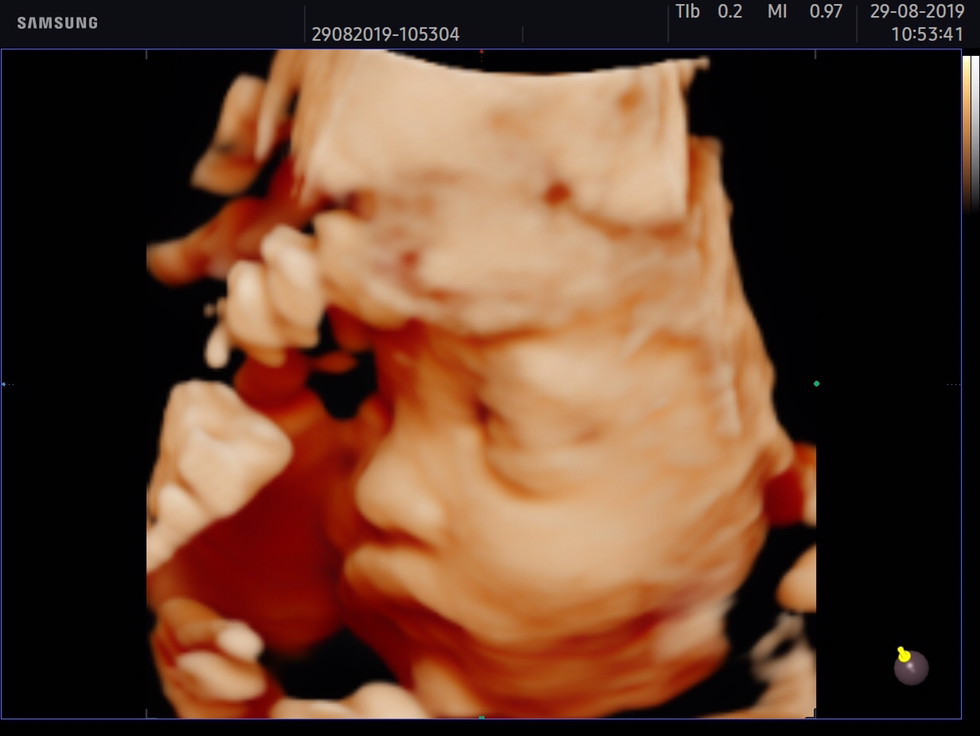

29 วีคค่ะ